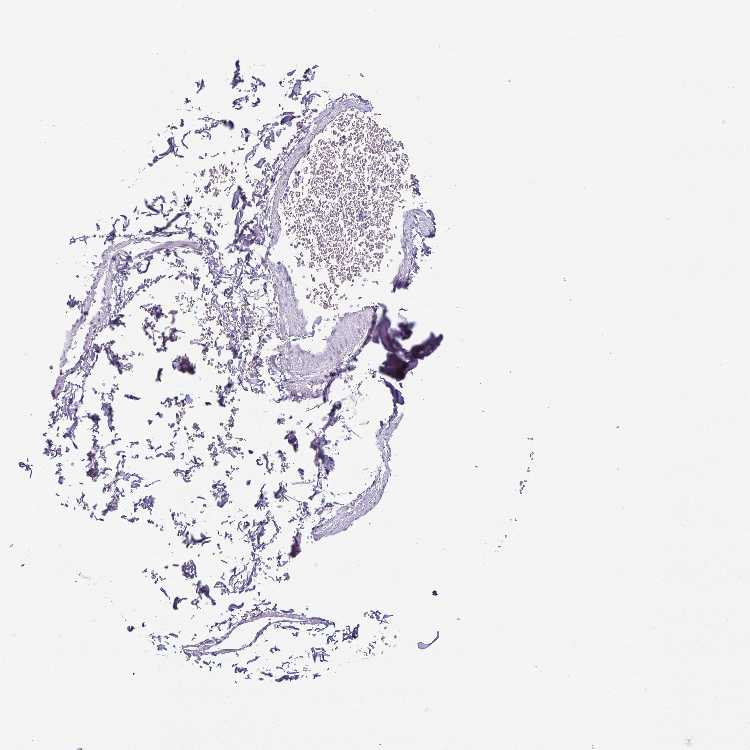

SOFT TISSUE 1 - Antibody stainingi

Antibody staining in the annotated cell types in the current human tissue is reported as not detected, low, medium, or high, based on conventional immunohistochemistry profiling in selected tissues. This score is based on the combination of the staining intensity and fraction of stained cells.

Each image is clickable and will lead to virtual microscopy that enables deeper exploration of all samples and also displays staining intensity scores, fraction scores and subcellular localization as well as patient and tissue information for each sample.

Antibody HPA037593Antibody HPA037594Antibody HPA061503

Chondrocytes Not detectedNot detectedNot detected

Fibroblasts Not detectedNot detectedNot detected

SOFT TISSUE 2 - Antibody stainingi

Peripheral nerve Not detectedNot detectedNot detected